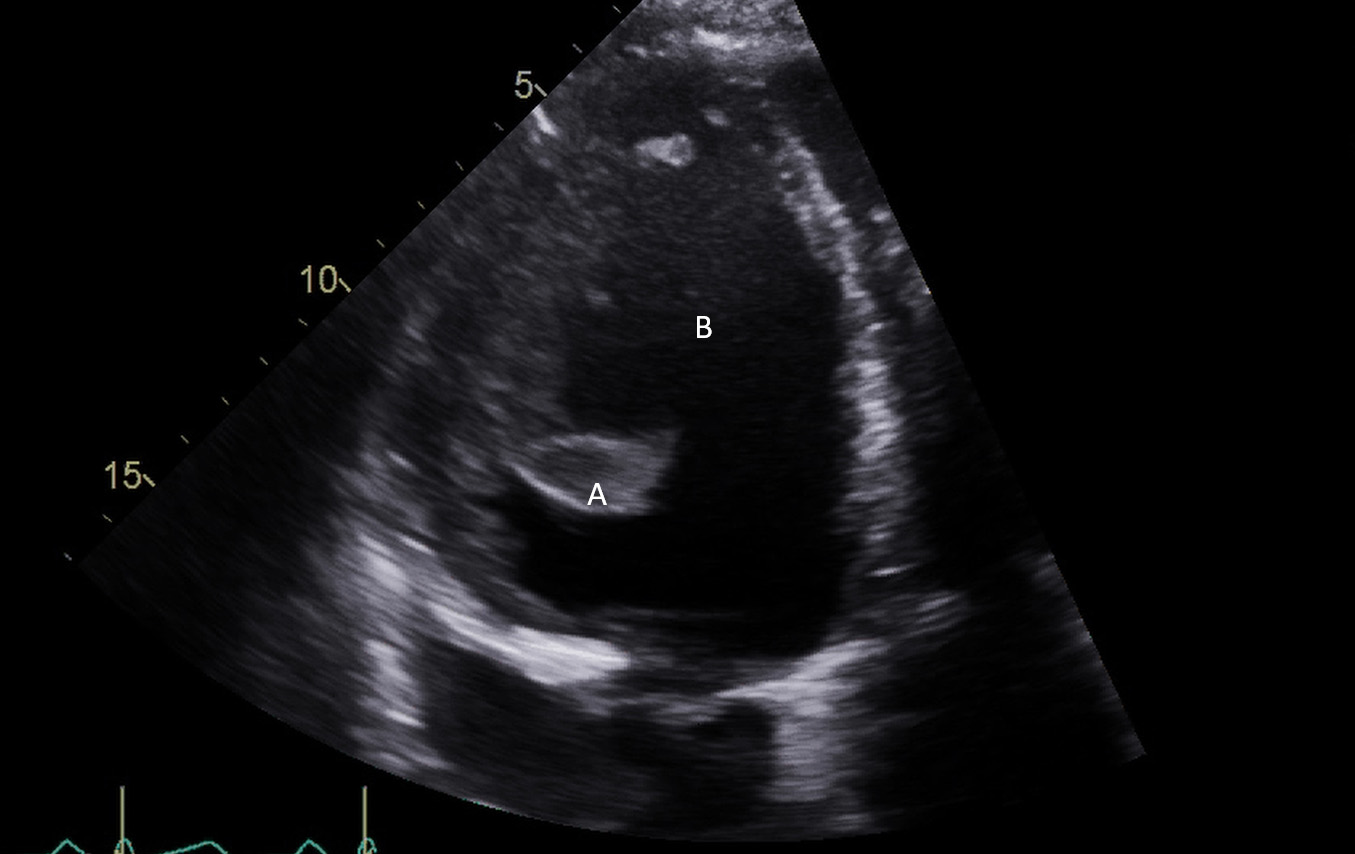

After initial access is obtained with a guidewire, TEE can confirm placement of the guidewire within the aorta and ensure there is no iatrogenic dissection from the procedure. The midesophageal long axis and 4 chamber views can be used to visualize the guidewire crossing of the aortic valve and positioning within the LV cavity. The wire tip should point towards the LV apex. Wire placement too deep within the LV can trigger ventricular arrhythmias and tethering of the mitral valve or subvalvular apparatus should be avoided as this can result in the inlet abutting the mitral valve or damage to subvalvular apparatus (Figs. 3,4) [13]. When the proceduralist is advancing the Impella over the guidewire, the best view to observe the device crossing the aortic valve is the midesophageal long axis view [13].

Impella (A) in the LV cavity caused disruption and damage to subvalvular apparatus resulting in flail segment (B) of the mitral valve.

Fig. 4.Impella (A) placement causing disruption and damage to subvalvular apparatus resulting in mitral valve flail (B) and mitral regurgitation (C).